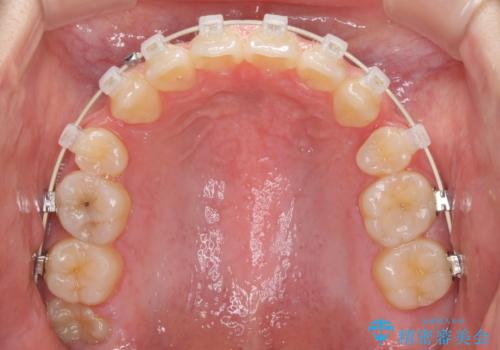

- 矯正装置

- 審美装置

- 3年3ヶ月

- 10-30回

上下前歯の前後位置が大きくずれていたため、上顎左右第一小臼歯2本を抜歯してワイヤー装置による矯正治療を行うこととしました。